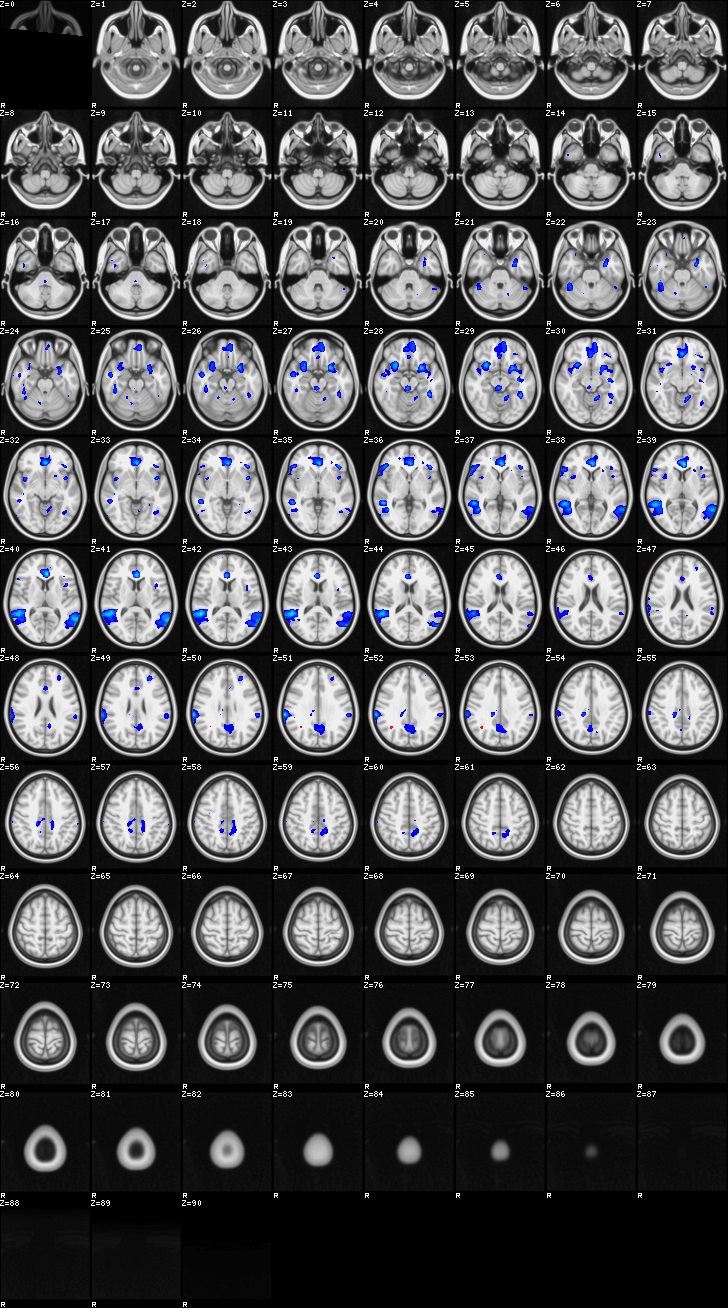

Mixed Effect (flame1)¶

ATM it is 26 subjects, 8 mm FWHM spatial (simple gaussian) smoothing, preliminary results only

Images thresholded abs value > 2.3 and colormap goes from 2.3 to 5 (red->yellow) or -2.3 to -5 (blue->lightblue)

01-FltC¶